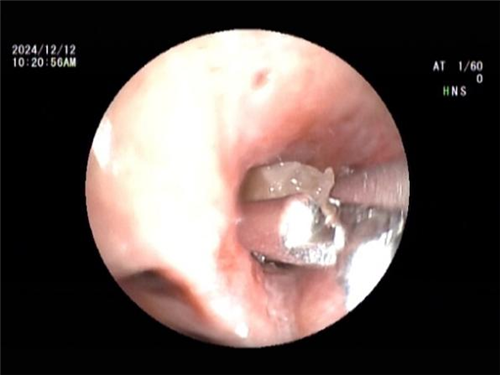

王海龙主任迅速组织团队对孟某展开全面综合评估,结合患者症状及各项检查结果,高度怀疑其患有吸入性气管异物并由此引发阻塞性肺炎。在与孟某及其家属进行充分且细致的沟通交流后,王海龙主任决定亲自为患者实施电子支气管镜检查。在支气管镜深入探查过程中,清晰可见患者右中叶支气管被一异物牢牢阻塞管腔。此异物表面光滑,质地极为脆弱,不仅易碎,还容易软化变形,这一系列棘手问题使得异物取出难度呈指数级增加。手术过程中,任何细微的失误都可能导致异物掉落至气管深部,从而引发更为严重且复杂的后果。但王海龙主任凭借其精湛高超的医术与沉稳冷静的临场应变能力,运用异物钳小心翼翼地进行操作,经过多次精准尝试,最终成功取出一枚长径约 1cm 的异物。术后,孟某的呼吸即刻恢复通畅,经过 5 天系统且精心的治疗,咳嗽、咳痰症状显著缓解,胸闷、气促等不适症状全然消失,肺部感染病灶也得到明显吸收。经确认,此次引发孟某一系列病痛的 “罪魁祸首” 竟是一粒花生米。